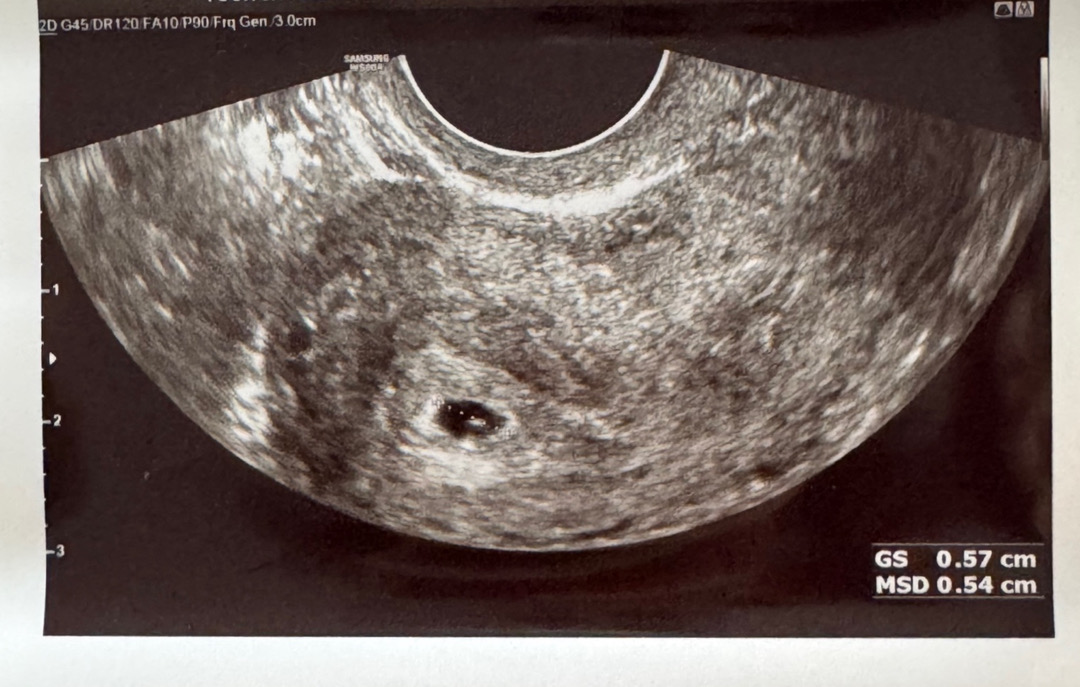

임신 5주 3일째 아기집 0.57cm 크기 정상일까요?

청담마리에서 8월 9일에 아기집 난황 확인하고 임신 확인서 받았는데 초음파 사진은 안 주셔서 오늘 8월 12일 집근처 병원에서 초음파 봤는데 크기가 0.57cm 이라서 작은 편이라고 하더라구요ㅠㅠ 청담마리 사이즈는 기억이 나지 않는데 저는 1.0cm 였던거 같이서요 신랑도 기억이 잘 인 난대요 이 주수에 사이즈 괜찮을까요? 경험 있는 분들 알려주세요